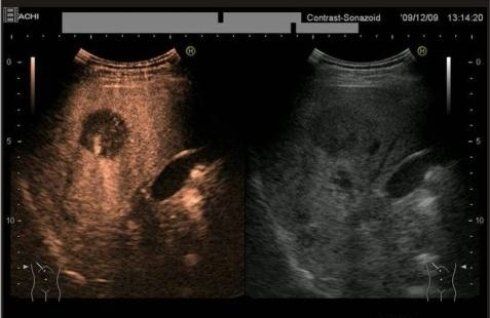

Lo studio radiologico del Dott. Famiglietti Gianfranco, specialista in radiologia diagnostica si occupa di ecotomografia, mammografia e densitometria ossea. I nostri macchinari sono tutti di ultima generazione per garantire ai nostri pazienti il miglior risultato con l'esposizione alla quantità di radiazioni più bassa possibile.

L'altissima qualità dei nostri macchinari ci permette di eseguire esami di ottima qualità in prima battuta riducendo al minimo la necessità di ripetizione e quindi ancora una volta l'esposizione del paziente a radiazioni inutili.